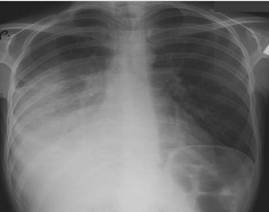

Науқас 25 жаста, жіті ауырып қалды. Безгектік және құрѓақ жөтел пайда болды, оң жақ бүйірінен ауырсыну қосылды. Оң жақ өкпенің астын перкуссиялағанда өкпе дыбысы женіл әлсіреді, аускультацияда дем алуы бәсең. Кеуде қуысы мөшелеріне 2-і стандартты проекцияда рентгенография тағайындалды.

Нақты клиникорентгенологиялық сурет қай ауруға сәйкес келеді:

A) Кавернозды өкпе туберкулезіне

{Дұрыс жауабы} = C